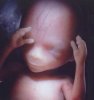

Что происходит на двадцатой неделе беременности? На двадцатой неделе беременности длина плода от темени до крестца составляет 14-16 см. Ваш малыш сейчас весит около 260 г.

На голове малыша уже различимы волоски и даже возможно определить цвет его волос. Продолжает накапливаться подкожный жир, при этом на лице его образование идет медленнее, поэтому пока имеются складочки на коже, за счет этого личико ребенка напоминает старческое. На 20-ой неделе беременности повышается активность плода, его движения становятся более разнообразны.